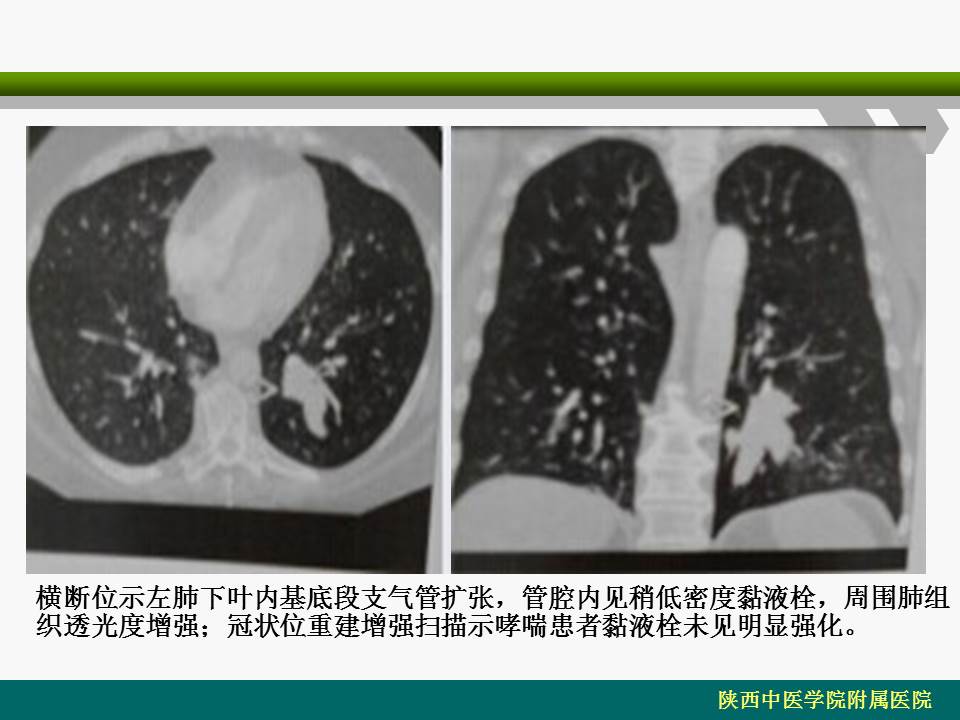

【PPT】支气管黏液栓